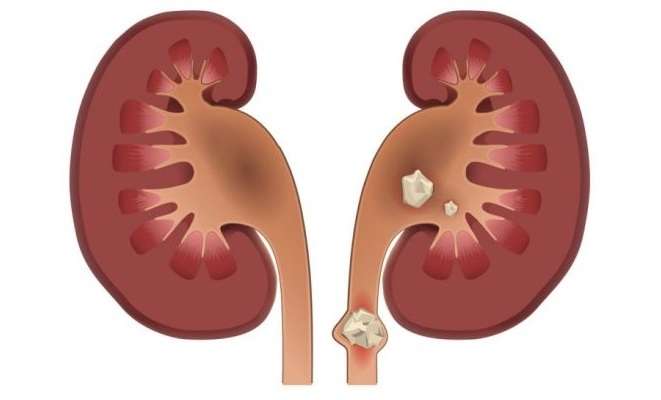

Камни в почках: неожиданные причины появления

Медики рассказали о том, что провоцирует создание камней в организме

Эксперты в области урологии назвали шесть странных на первый взгляд вещей, которые могут спровоцировать появление камней в почках. К ним относится даже проживание в тропическом климате.

"Комментарии" приводят все шесть причин, ссылаясь на информагенство "Аптека 24".

Нехватка кальция в рационе. Множество камней в почках состоят из кальция, из-за чего люди часто отказываются от данного питательного элемента. Но это большая ошибка, потому что исключение продуктов с кальцием ... увеличивает риск мочекаменной болезни, как подтвердило исследование ученых из Гарвардской школы здравоохранения. Следуйте правильного баланса кальция, и вероятность камней в почках будет минимальной.

Употребление слишком большого количества мяса. Если вы жить не можете без этого продукта, то, по крайней мере, чаще налегайте на белое, а не красное мясо. В 2014 году ученые подтвердили, что мясоеды на 30-50% чаще сталкиваются с камнями в почках по сравнению с вегетарианцами.

Проживание в тропиках. Если вы живете в тропическом климате, то риск мочекаменной болезни растет. Это связано с более низким оттоком мочи из организма, особенно если люди испытывают недостаток питьевой воды. Хроническая диарея, часто наблюдается среди жителей бедных тропических стран, также увеличивает вероятность камней в почках.

Глобальное потепление и изменения климата. Наука давно ведет споры о том, существует ли связь между глобальным потеплением и появлением камней в почках. Чем жарче погода, тем выше риск мочекаменной болезни, доказывает статистика из разных стран мира. Однако все еще не установлен прямой причинно-следственная связь между этими явлениями.

Генетика. Так называемые цистиновые камни, которые являются одним из видов камней в почках, представляют собой следствие слишком большого количества субстанции цистина в моче. А она появляется там через цистинурии — генетическое расстройство, который вы наследуете от родителей. Это единственный вид камней в почках, который передается генетическим путем.

Синдром раздраженного кишечника. В число недугов, которые попадают под эту категорию, обычно включают язвенный колит и болезнь Крона. Однако несколько исследований показали, что в этот список также должна попасть мочекаменная болезнь. Одна из причин этого — диарея, связанная с нарушениями в работе желудка, которая лишает организм воды.